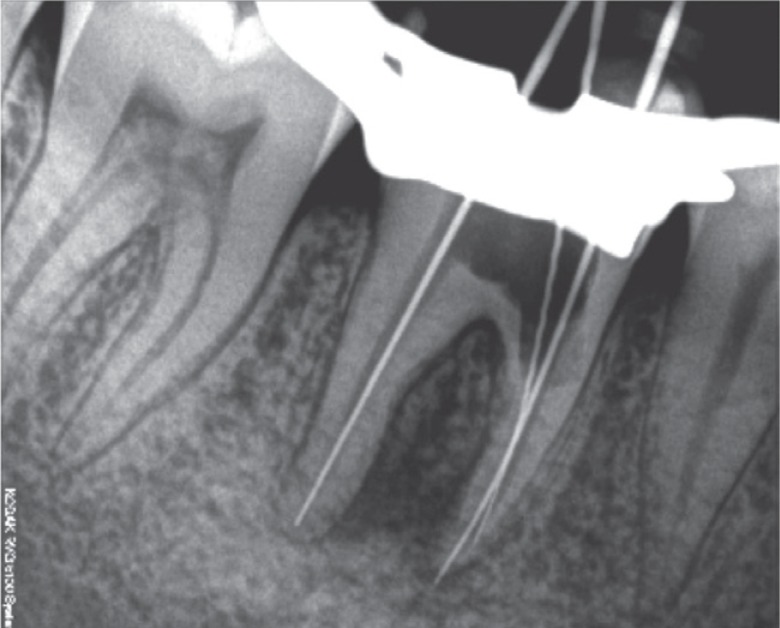

Based on the clinical and radiographic findings, a treatment plan was made. Endodontic therapy was initiated (

Figure 3Working length determination radiograph.